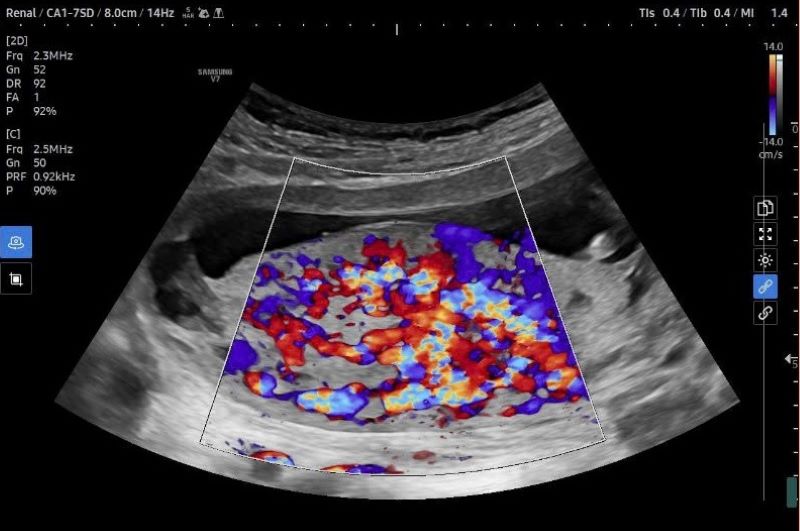

Hình ảnh siêu âm thai của bệnh nhân cho thấy tình trạng nhau cài răng lược

Trong lần thăm khám thai định kỳ thứ hai khi thai được 13 tuần 4 ngày tại MEDLATEC Gò Vấp, thai phụ L.T.K.H (30 tuổi, TP. Hồ Chí Minh) bất ngờ được chẩn đoán theo dõi nhau cài răng lược. Đây là một biến chứng nguy hiểm trong thai kỳ được bác sĩ phát hiện thông qua quá trình siêu âm thai.

Ngay sau đó, ekip bác sĩ tại MEDLATEC đã tiến hành hội chẩn khẩn cấp và tư vấn cho sản phụ về nguy cơ cao trong thai kỳ. Trường hợp này được đánh giá đặc biệt phức tạp bởi phát hiện ở giai đoạn rất sớm, nguy cơ tiến triển nặng và đòi hỏi quá trình theo dõi kéo dài, liên tục giữa bác sĩ và gia đình.

Theo bác sĩ Trần Thị Yến Nhi, nhau cài răng lược là bệnh lý nguy hiểm nhưng thường không có triệu chứng rõ ràng. Nếu chỉ dựa vào biểu hiện lâm sàng, thai phụ và gia đình rất khó nhận biết. Nhờ có siêu âm sản khoa và các phương tiện chẩn đoán hình ảnh hiện đại, bác sĩ có thể phát hiện những dấu hiệu bất thường của bánh nhau ngay từ giai đoạn sớm. Điều này cho phép xây dựng kế hoạch theo dõi và can thiệp phù hợp, giảm thiểu tối đa nguy cơ biến chứng nặng.